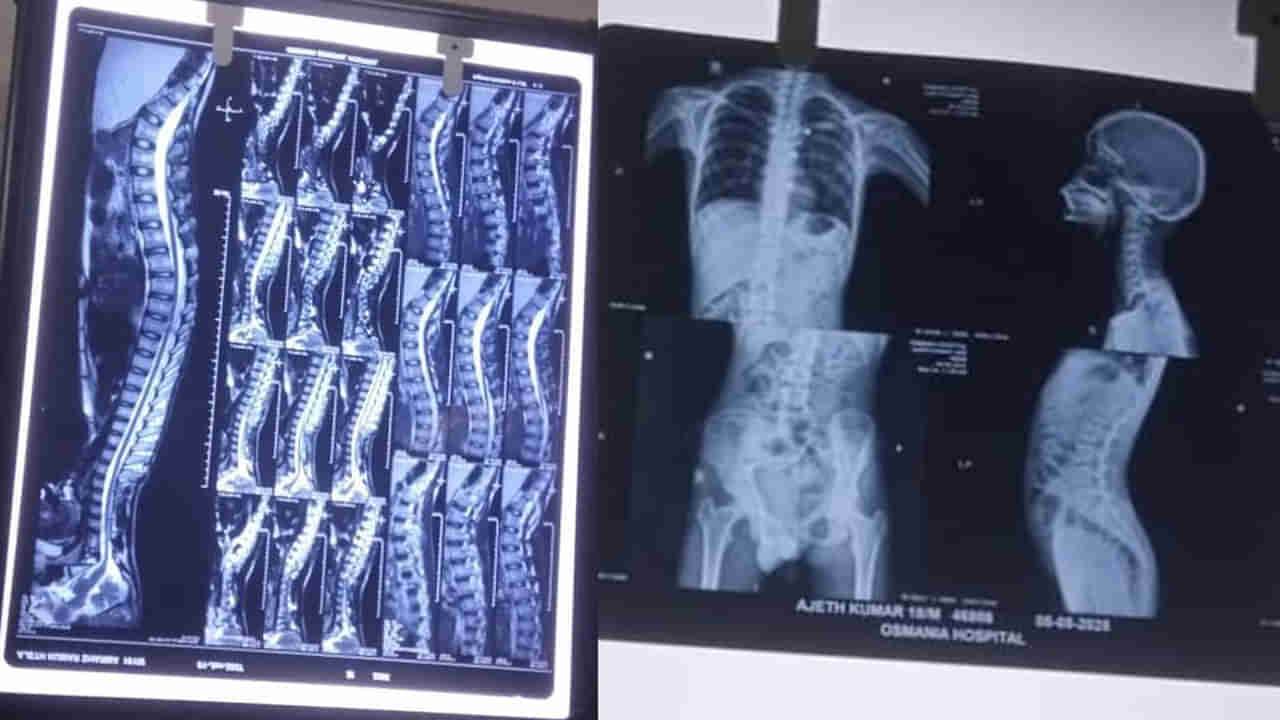

ఆరు నెలలుగా హాస్పిటల్స్ చుట్టూ తిరుగుతున్నామని అయిన కూడా ఆరోగ్యం కుదుట పడడంలేదని కాళ్లు చచ్చుపడి మంచానికే పరిమితమయ్యడని బాలుడి తల్లి దగ్గుపాటి కనకదుర్గ చెబుతోంది. ఉస్మానియా ఆసుపత్రిలో చికిత్సకు తీసుకెళ్లినా నయం కావడం లేదని ఆవేదన వ్యక్తం చేస్తుంది. తన కొడుకు గతంలో చురుకుగా ఆటలు ఆడేవాడని, NCCలో చురుకుగా పాల్గొనేవాడని.. స్టేషన్లో పోలీసులు తన కొడుకు జీవిత నాశనం చేశారని వారిపై కఠిన చర్యలు తీసుకోవాలని కోరుతుంది బాలుడి తల్లి.